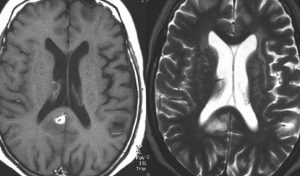

MRI検査で,はっきりわかります。MRI造影剤を入れると均一または斑らに増強(真っ白になる)されて(左側),周囲には脳の腫れ(脳浮腫)がみられます(右側)。できやすい場所は側脳室の周囲・大脳脳基底核・小脳・脳幹部など脳の深いところ(深部白質)です。脳の中に2個以上のリンパ腫が同時にできる多発例というのもしばしばあります